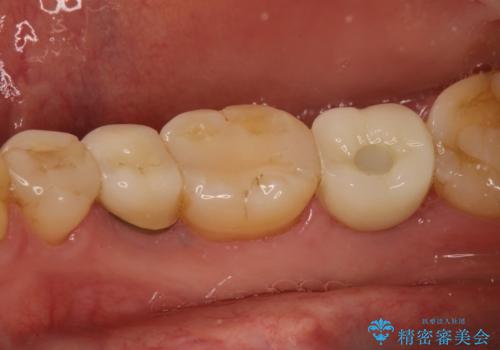

インプラント治療により、周りの歯を削ることなく咬合を回復することができました。